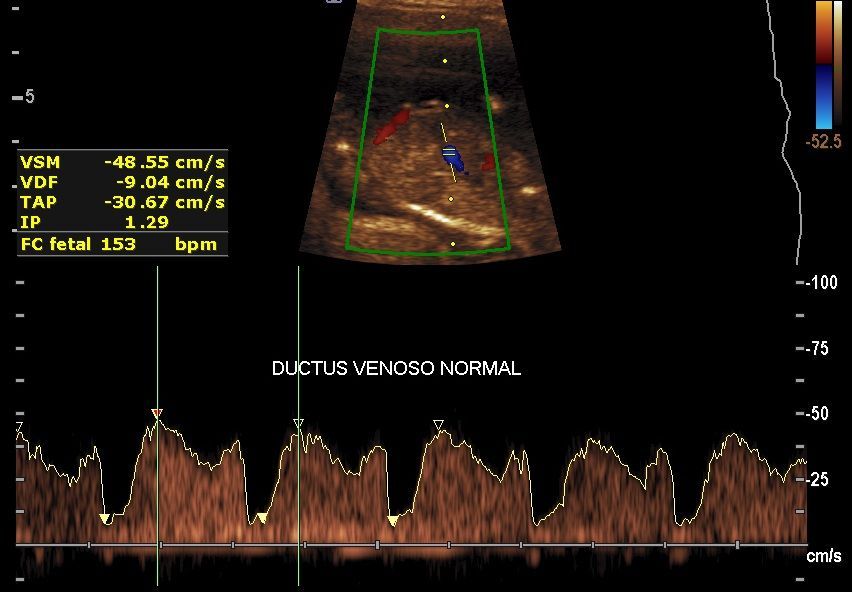

Realizamos las ecografías de viabilidad del embarazo, genética, morfológica, de bienestar fetal, ecocardiografías fetales, así como procedimientos invasivos como biopsia de vellosidades coriales y amniocentesis.